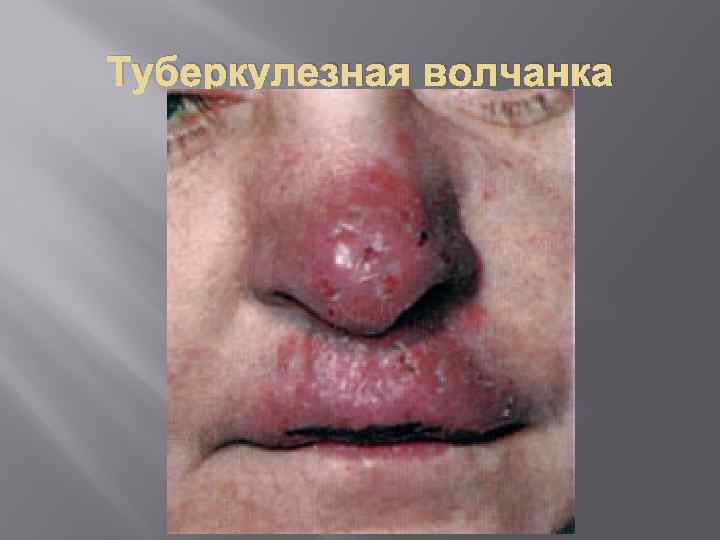

Туберкулезная волчанка, или волчаночный туберкулез кожи, развивается при заносе микобактерии туберкулеза в кожу гематогенным и лимфогенным путем. На коже лица (нос, губы, щеки, ушные раковины и др. ), на слизистой оболочке носа и рта, реже на коже туловища и конечностях появляются мягкие красновато-оранжевые бугорки диаметром от 0, 2 до 0, 8 см. Сливаясь, они образуют более крупные очаги поражения Колликвативный туберкулез кожи, или скрофулодерма, развивается вследствие попадания в кожу микобактерий туберкулеза преимущественно лимфогенным путем и по соприкосновению (из лимфатических узлов, суставов). Характеризуется появлением в дерме (собственно коже) и подкожной основе шаровидного узла диаметром 0, 5– 3 см. Чаще узел располагается в области крупных лимфатических узлов (поднижнечелюстных, шейных, подмышечных, паховых) и по краю грудины. Вначале узел небольшой, подвижный. Постепенно он увеличивается и спаивается с окружающими тканями. Кожа над ним истончается, приобретает синюшно-красный цвет. Затем узел некротизируется и прорывается в нескольких местах наружу с выделением жидкого гноя и крошковатых масс. После заживления остаются характерные неровные рубцы с «сосочками» и «мостиками» , позволяющие безошибочно ретроспективно установить перенесенный колликвативный туберкулез кожи.

Туберкулезная волчанка, или волчаночный туберкулез кожи, развивается при заносе микобактерии туберкулеза в кожу гематогенным и лимфогенным путем. На коже лица (нос, губы, щеки, ушные раковины и др. ), на слизистой оболочке носа и рта, реже на коже туловища и конечностях появляются мягкие красновато-оранжевые бугорки диаметром от 0, 2 до 0, 8 см. Сливаясь, они образуют более крупные очаги поражения Колликвативный туберкулез кожи, или скрофулодерма, развивается вследствие попадания в кожу микобактерий туберкулеза преимущественно лимфогенным путем и по соприкосновению (из лимфатических узлов, суставов). Характеризуется появлением в дерме (собственно коже) и подкожной основе шаровидного узла диаметром 0, 5– 3 см. Чаще узел располагается в области крупных лимфатических узлов (поднижнечелюстных, шейных, подмышечных, паховых) и по краю грудины. Вначале узел небольшой, подвижный. Постепенно он увеличивается и спаивается с окружающими тканями. Кожа над ним истончается, приобретает синюшно-красный цвет. Затем узел некротизируется и прорывается в нескольких местах наружу с выделением жидкого гноя и крошковатых масс. После заживления остаются характерные неровные рубцы с «сосочками» и «мостиками» , позволяющие безошибочно ретроспективно установить перенесенный колликвативный туберкулез кожи.